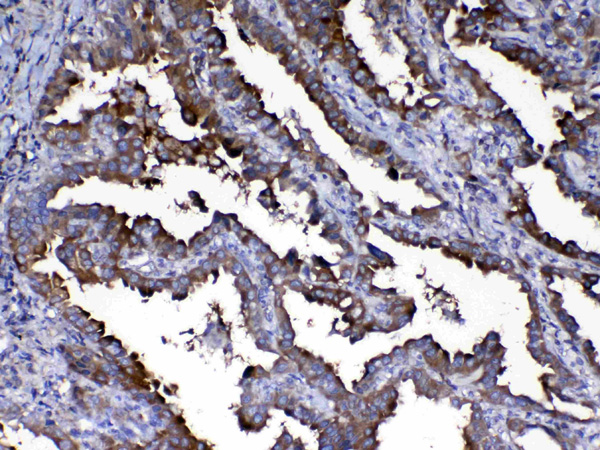

IHC (Immunohistochemisry)

(Figure 3. IHC analysis of Calpain 2 using anti-Calpain 2 antibody (AAA124708).Calpain 2 was detected in paraffin-embedded section of human lung cancer tissue. Heat mediated antigen retrieval was performed in citrate buffer (pH6, epitope retrieval solution) for 20 mins. The tissue section was blocked with 10% goat serum. The tissue section was then incubated with 1ug/ml rabbit anti-Calpain 2 Antibody (AAA124708) overnight at 4 degree C. Biotinylated goat anti-rabbit IgG was used as secondary antibody and incubated for 30 minutes at 37 degree C. The tissue section was developed using Strepavidin-Biotin-Complex (SABC) with DAB as the chromogen.)